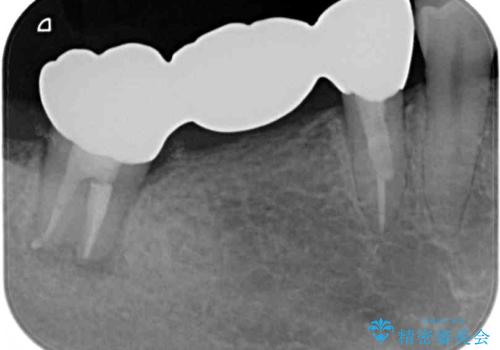

根管治療実施後は速やかに痛みが引き、仮歯で食事を取っても痛むことはなくなりました。

親知らずもむし歯が進行していたため、抜歯をし、傷の治りを待ってブリッジによる補綴治療を行いました。